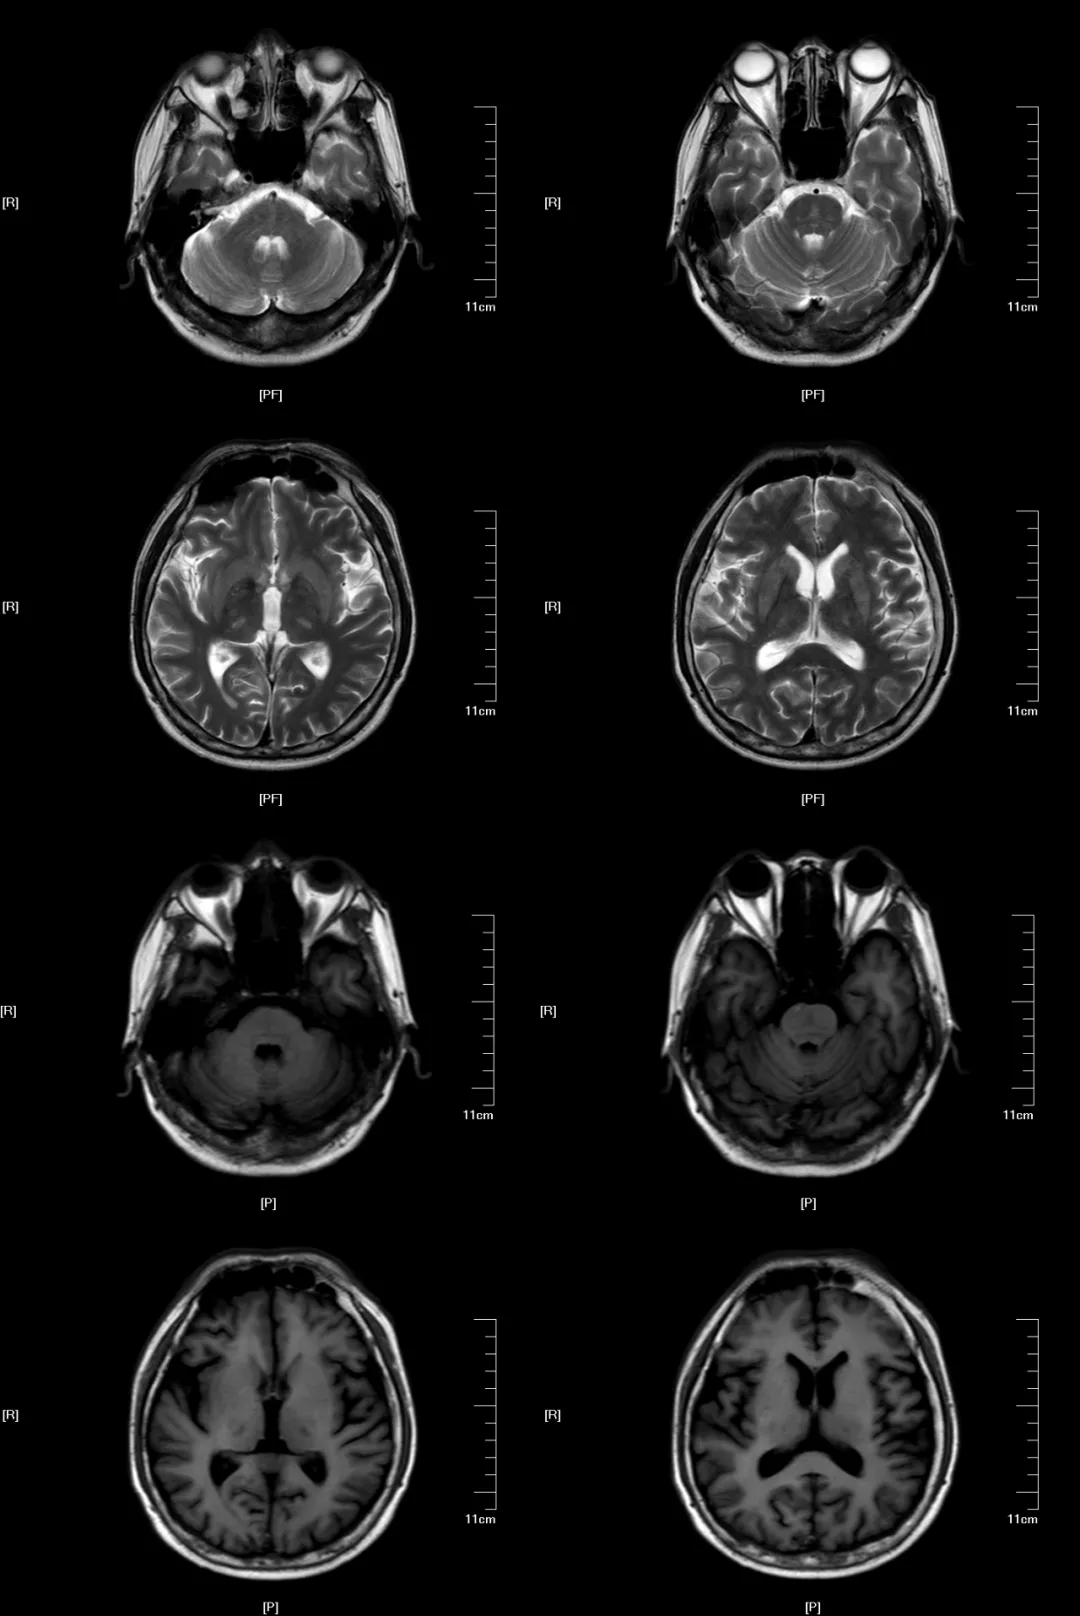

病例展示中枢神经系统脱髓鞘疾病是一组脑和脊髓以髓鞘破坏或髓鞘脱失

脑脱髓鞘疾病的影像诊断

脑脱髓鞘疾病的影像诊断 | 影像天地